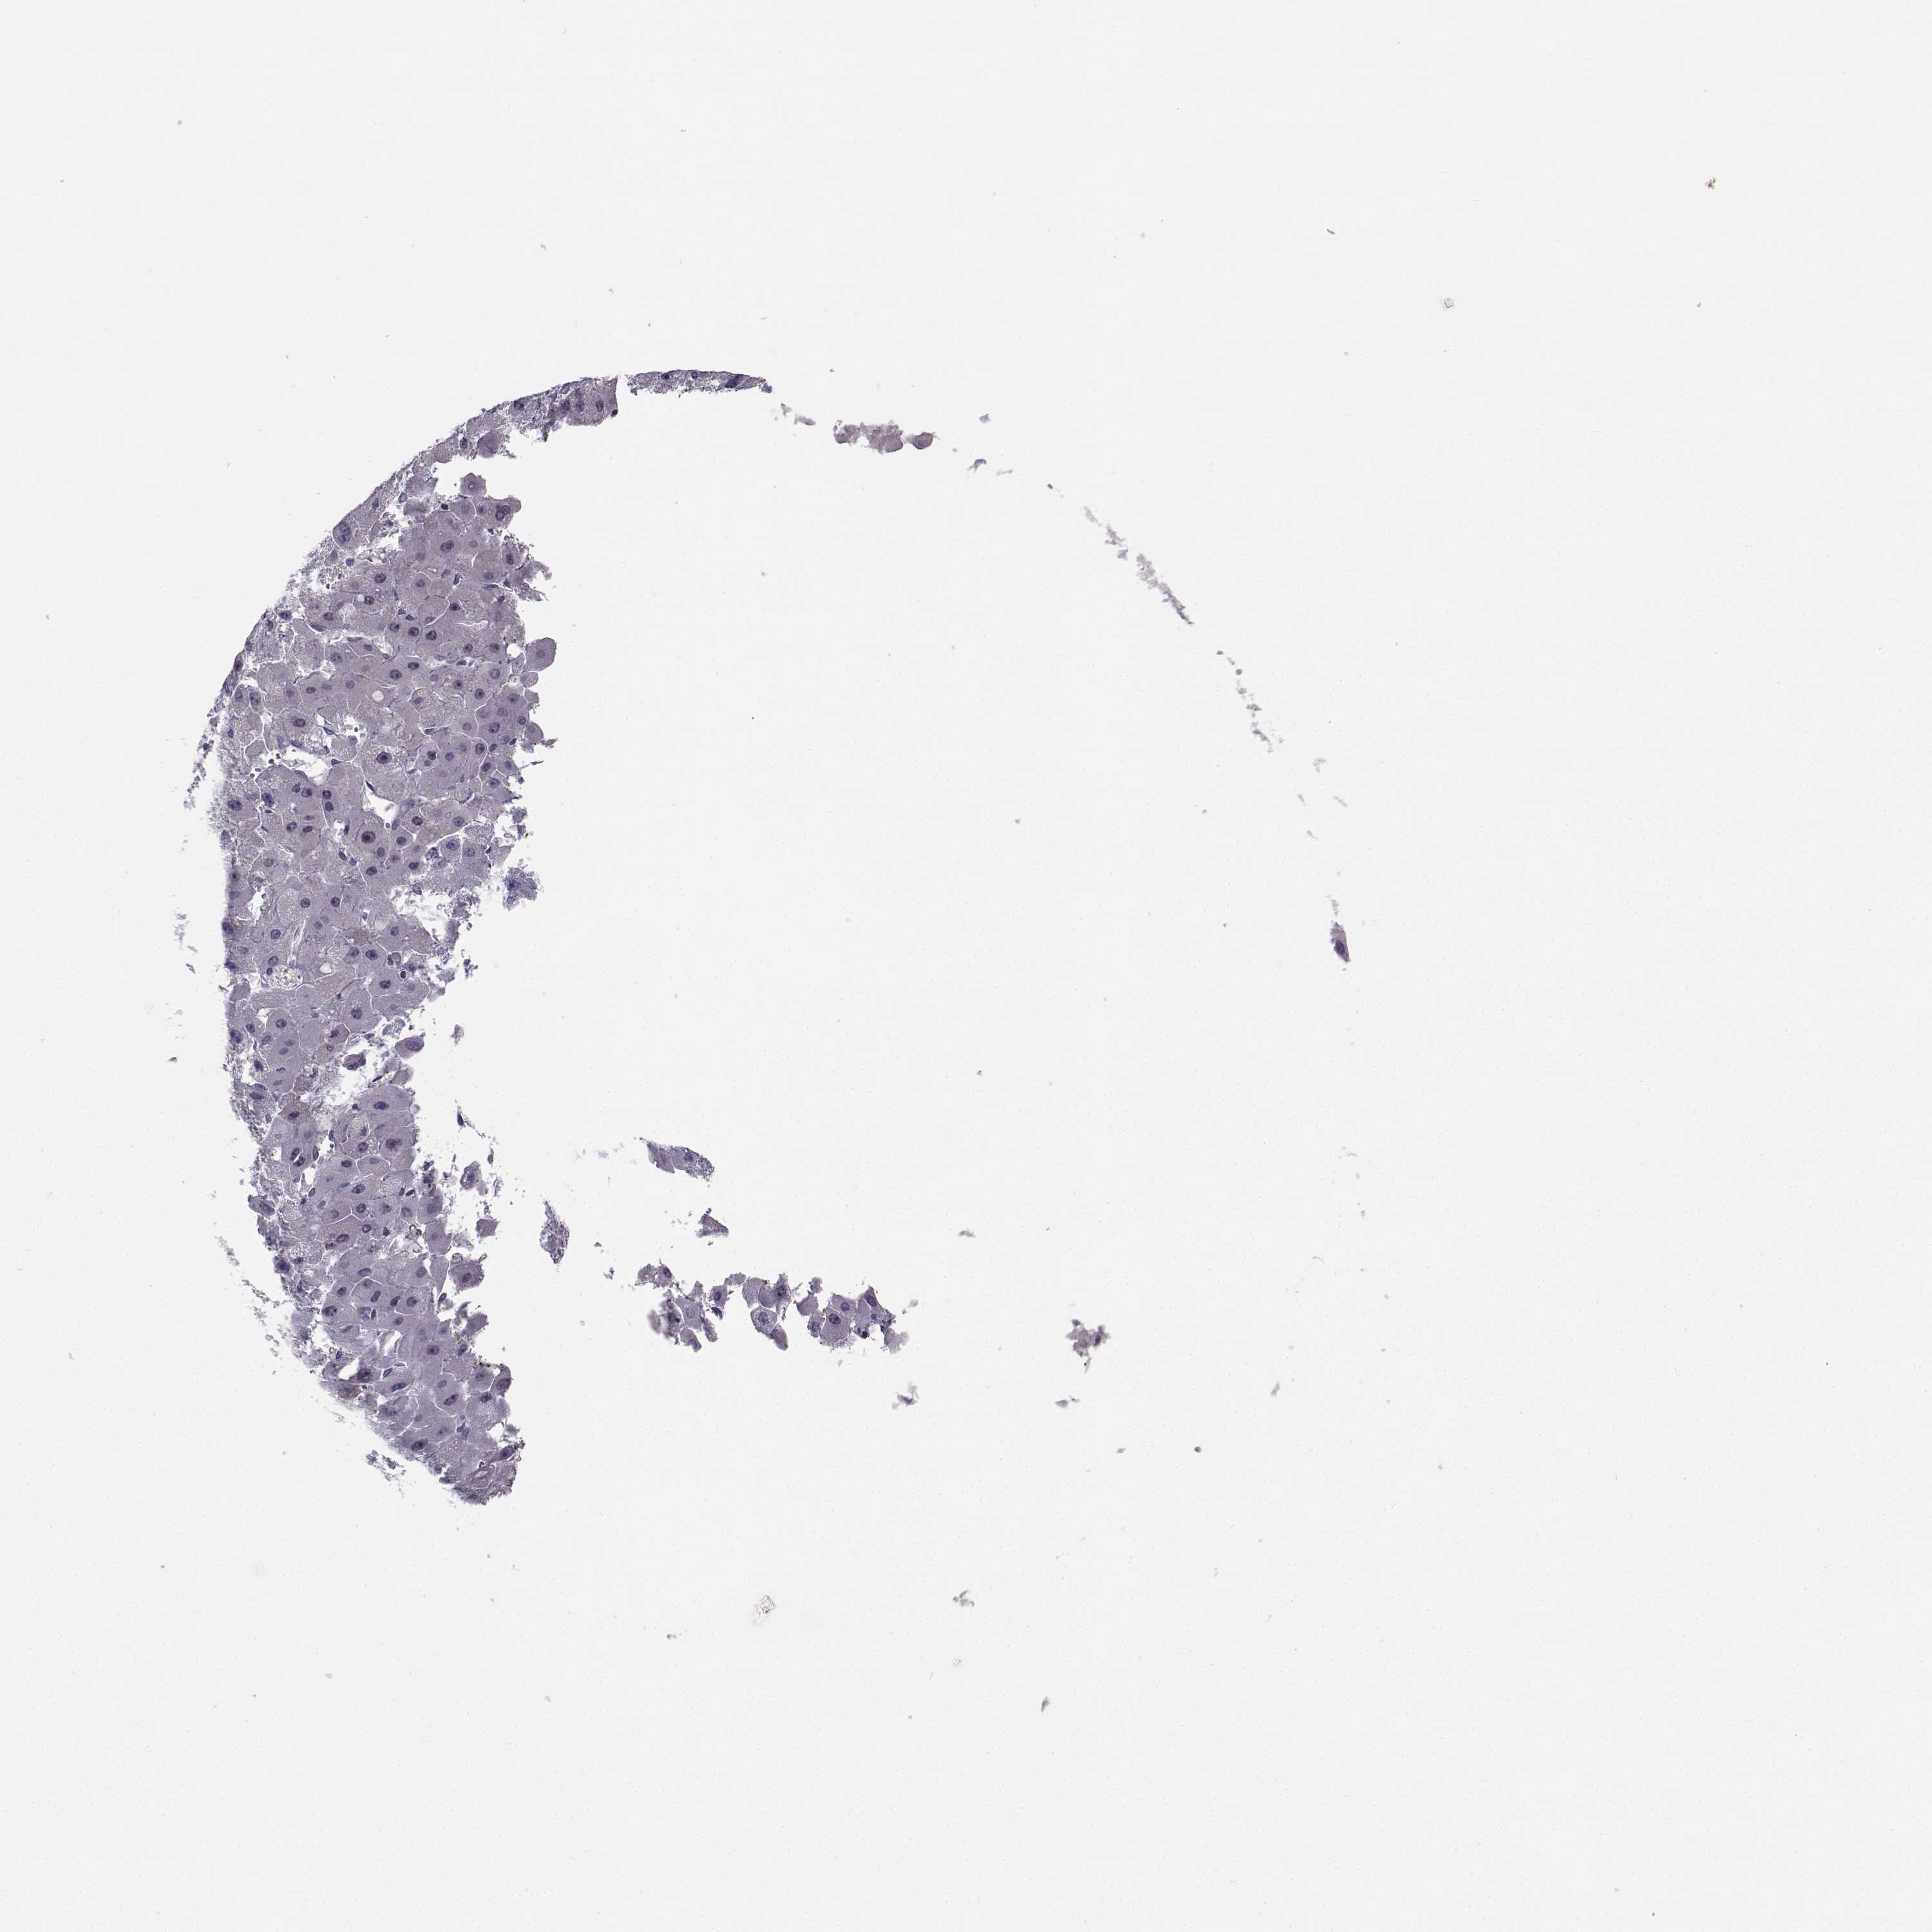

LIVER CANCER - Protein expressioni

A mouse-over function shows sample information and annotation data. Click on an image to view it in a full screen mode. Samples can be filtered based on level of antibody staining by selecting one or several of the following categories: high, medium, low and not detected. The assay and annotation is described here.

Note that samples used for immunohistochemistry by the Human Protein Atlas do not correspond to samples in the TCGA dataset.

Antibody stainingi

Antibody staining in the annotated cell types in the current human tissue is reported as not detected, low, medium, or high, based on conventional immunohistochemistry profiling in selected tissues. This score is based on the combination of the staining intensity and fraction of stained cells.

Each image is clickable and will lead to virtual microscopy that enables deeper exploration of all samples and also displays staining intensity scores, fraction scores and subcellular localization as well as patient and tissue information for each sample.

Antibody HPA073031

Staining

High

Medium

Low

Not detected

Intensity

Strong

Moderate

Weak

Negative

Quantity

>75%

75%-25%

<25%

None

Location

Nuclear

Cytoplasmic/membranous

Cytoplasmic/membranous,nuclear

Carcinoma, Hepatocellular, NOS

Cholangiocarcinoma